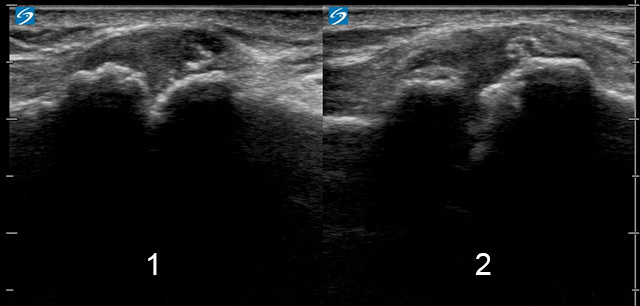

1. Compressed-patient moves ipsilateral palm to cover the contralateral anterior humeral head

2. Neutral-arm hanging at side